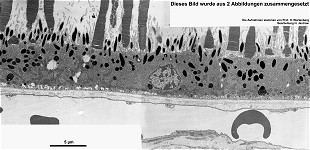

pigment epithelium and rod

outer segments (W, monkey)

pigment epithelium, Bruch's membrane

+ choroidea (W, monkey)